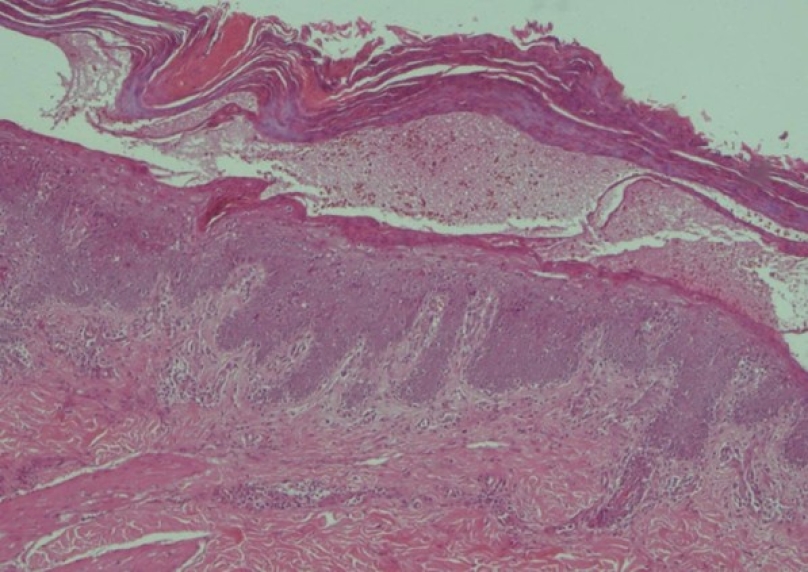

Bệnh nhân được tiến hành sinh thiết da hai lần. Kết quả giải phẫu bệnh lần 1 (01/2026) cho thấy hình ảnh tăng sản thượng bì dạng vảy nến, kèm theo nhiều tế bào dị sừng. Kết quả lần 2 (03/2026) ghi nhận thượng bì tăng sản dạng vảy nến, dày sừng và á sừng, kèm theo phản ứng viêm dạng lichen và tăng sinh collagen. Nhiều tế bào dị sừng (dyskeratotic cells) xuất hiện rải rác trong lớp gai. Nhuộm Masson ba màu xác nhận tình trạng tăng sinh collagen lan tỏa tại trung bì.

Về mặt mô bệnh học, dấu hiệu then chốt để xác định TAMA là hiện tượng interface dermatitis kèm theo các tế bào dị sừng (dyskeratotic cells). Cơ chế này đã được làm rõ trong các nghiên cứu của Miyagaki et al. (2013), theo đó các lympho bào T CD8+ xâm thâm nhiễm lớp đáy thượng bì và kích hoạt quá trình chết tế bào theo chương trình (apoptosis) của các tế bào gai. Đây là đặc điểm tương đồng với bệnh Ghép chống chủ (GvHD), gợi ý rằng khối u tuyến ức đã tạo ra một môi trường nơi các tế bào T không còn khả năng phân biệt giữa kháng nguyên tự thân và kháng nguyên ngoại lai.